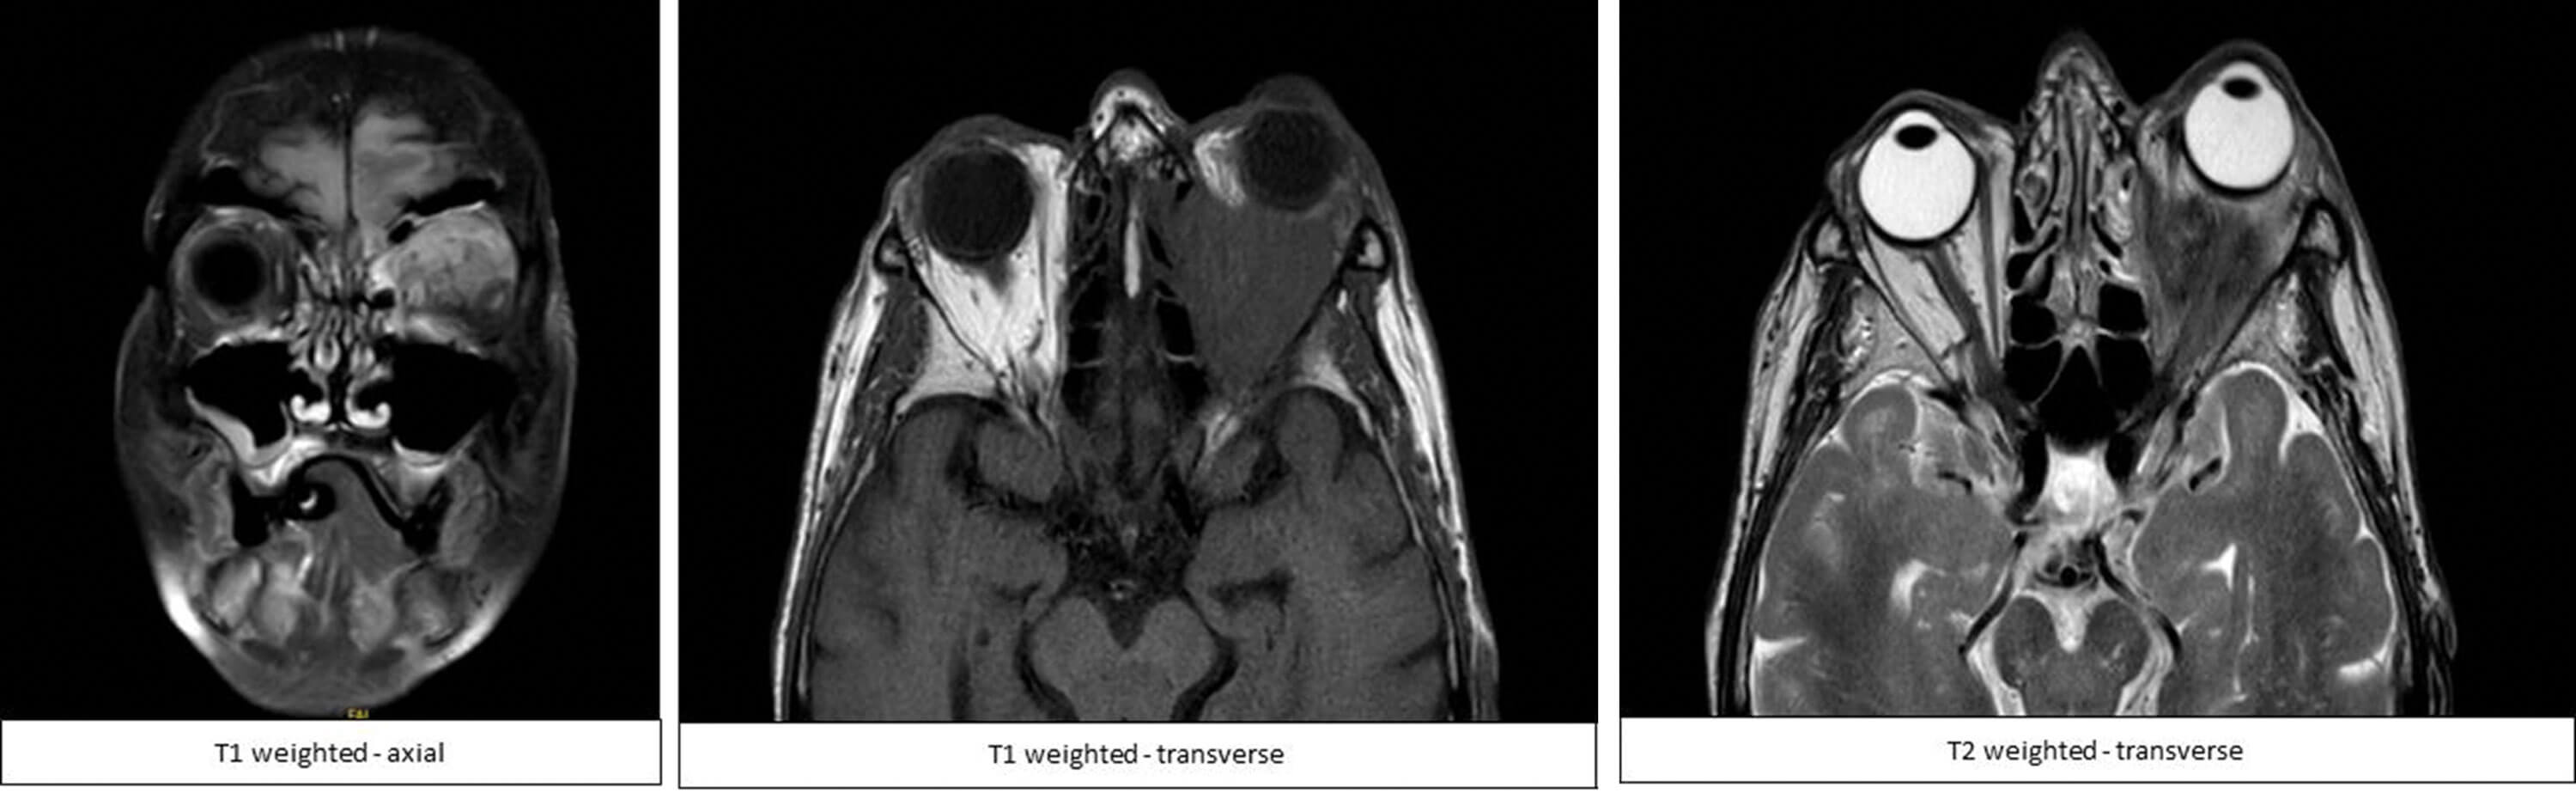

An 89-year-old woman presented to her GP with pain and swelling to the left eyelid with ptosis and hyper-lacrimation. This further followed with reduced sensation and numbness in the eyebrow and left part of the lip. She was initially diagnosed with Bell’s palsy. She subsequently had an MRI brain and MRI orbits which showed a low-signal soft tissue mass posteriorly and superiorly in the conus of the left orbit (Figure 1).

Figure 1: MRI head and orbit images of patient: (a) Axial T1 weighted image;

(b) Transverse T1 weighted image; (c) Transverse T2 weighted image.

The mass extended medially into the ethmoid sinus and nasal cavity and the superior rectus muscle was engulfed. She was referred to the ophthalmology department where she presented with a history of a painless progressive proptosis with ptosis on her left eye. Her past medical history was positive for goitre, but she didn’t experience nose bleeding, not a diabetic, no history of immunosuppression or trauma.